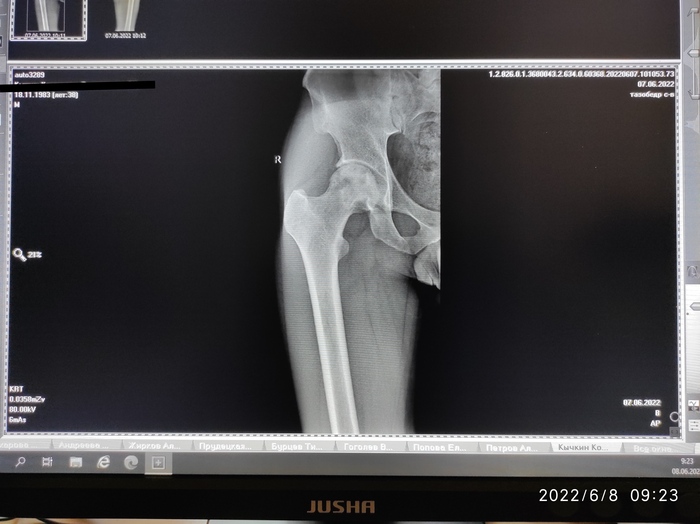

Сказали нужна операция

В общем сказали нужно менять головку бедренновой кости на железную. Пока пытаюсь записаться на консультацию в республиканскую больницу. Я пока ещё не совсем понимаю что за операция и долго ли проходит реабилитация. Кто сталкивался с таким прошу рассказать. У меня боли начались года 2 назад. Могу ответить в комментариях, если интересно.